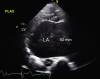

An Audaciously Aneurysmal Atrium

Keywords: Echocardiography; Imaging; Mitral stenosis; Rheumatic heart disease.